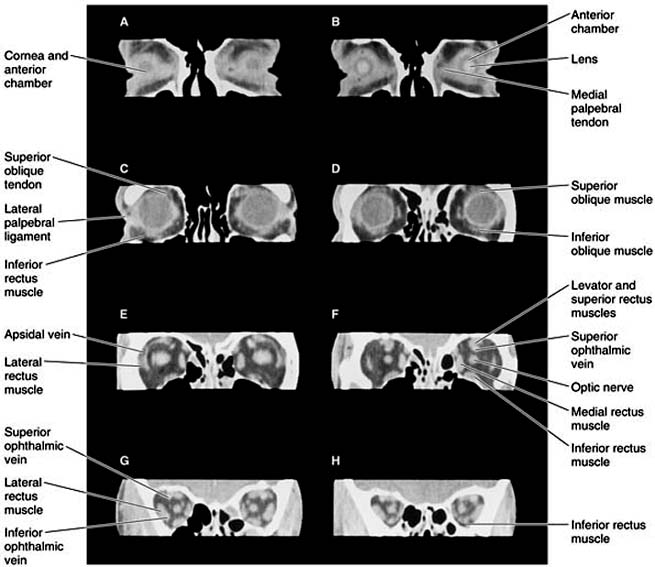

Chapter 13: Orbit Author: Orbit PHYSIOLOGY OF SYMPTOMS Owing to the rigid bony structure of the orbit, with only an anterior opening for expansion (Chapter 1), any increase in the orbital contents taking place to the side of or behind the eyeball will displace that organ forward (proptosis). Protrusion of the eyeball is the hallmark of orbital disease. Expansive lesions may be benign or malignant and may arise from bone, muscle, nerve, blood vessels, or connective tissue. A mass may be inflammatory, neoplastic, cystic, or vascular. Protrusion is not in itself injurious unless the lids are unable to cover the cornea. The underlying cause, however, is usually serious and sometimes life-threatening. Pseudoproptosis is apparent prop-tosis in the absence of orbital disease. Such confusion may arise with high myopia, buphthalmos, and lid retraction. History and examination provide many clues to the cause of proptosis. The position of the eye is determined by the location of the mass. Expansion within the muscle cone displaces the eye straight ahead (axial proptosis), whereas a mass arising outside the muscle cone will also cause sideways or vertical displacement of the globe directly away from the mass (nonaxial proptosis). Bilateral involvement generally indicates systemic disease, such as Graves' disease. The term "exophthalmos" is often used when describing proptosis associated with Graves' disease. Pulsating proptosis reflects the pulse of an orbital vascular malformation or transmission of cerebral pulsations in the absence of the superior orbital roof, as in neurofibromatosis-1. Positional proptosis-which changes with Valsalva's maneuver-is a sign of orbital varices or meningocele. Intermittent proptosis may be the result of a sinus mucocele. The Hertel exophthalmometer (see Chapter 2) is the standard method of quantifying the magnitude of proptosis. Serial measurements are most accurate if performed by the same individual with the same instrument. With the change in position of the eyeball, especially if it takes place rapidly, there may be enough mechanical interference with the movement of the eye to cause dissociation of ocular movements and diplopia (double vision). Pain may occur as a result of rapid expansion, inflammation, or infiltration of sensory nerves. Vision is not usually affected early unless the lesion arises from the optic nerve. Pupillary signs and color vision testing may identify subtle optic nerve compression or involvement before acuity is reduced significantly. Involvement of the superior orbital fissure by trauma or tumor produces a characteristic combination of diplopia resulting from disturbance of function of the oculomotor, trochlear, and abducens nerves and corneal and facial anesthesia (ophthalmic division of trigeminal nerve), known as the orbital fissure syndrome. Expanding lesions at the orbital apex result in the orbital apex syndrome, characterized by proptosis and optic nerve compression, variably accompanied by the diplopia and corneal and facial anesthesia seen in the orbital fissure syndrome. DIAGNOSTIC STUDIES 1. IMAGING Imaging by computed tomography (CT scan) (Figures 13-1 and 13-2) was a major advance in orbital diagnosis. Continued improvement in resolution quality-as well as three-dimensional reconstructions-have made CT the single most important diagnostic study in the investigation of orbital disease. Contrast enhancement with CT during study of vascular lesions sometimes provides additional information. Magnetic resonance imaging (MRI) is capable of displaying subtle changes within soft tissue that cannot be imaged with CT, but it is less useful for bony changes. A surface coil applied directly to the orbit enhances image resolution. MRI is contraindicated in the presence of a ferrous intraorbital or intracranial foreign body. Ultrasonography The use of ultrasonography in the diagnosis of orbital disease has largely been supplanted by CT and MRI. Although it is a noninvasive and inexpensive form of imaging, its usefulness in both A and B mode is limited to the anterior portion of the orbit. It is of greatest value in the hands of the clinician- ultrasonographer capable of interpreting "real time" images. Venography Venography is occasionally useful in defining the extent of orbital venous disease. Although the diagnosis can be made by MRI, contrast injection into the orbital veins via a scalp vein can sometimes reveal the presence of varices that have escaped detection by CT. Angiography Selective carotid angiography with bone subtraction is sometimes necessary to make the diagnosis of certain orbital vascular disorders. In spontaneous, low-flow dural carotid artery-cavernous sinus fistula, angiography is required for delineation of the extent of involvement and for treatment by embolization. Radiography Plain x-rays are sufficient for diagnosis of many orbital disorders such as fractures. However, the thin walls of the orbit are difficult to visualize even with tomography, and CT or MRI imaging is used to determine the extent of injury. Dacryocystography and radionuclide scanning can sometimes be helpful in localizing the site of lacrimal obstructions, but these procedures are seldom used. The results are difficult to interpret, and treatment is seldom altered by the findings. Positive contrast radiography and pneumo-orbitography are no longer used. Orbital thermography is a research procedure. Fine-Needle Aspiration Fine-needle aspiration is an invasive procedure that has proved very useful in orbital diagnosis. Cytology specimens can be aspirated from a lesion the exact location of which is determined by CT imaging. Cytopathology can be inconclusive but is often invaluable. Page 1 of 7 10.1036/1535-8860.ch13 |